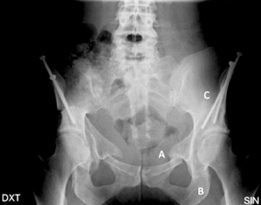

Key radiographic parameters are critical in quantifying the degree and pattern of dysplasia. These include the lateral center-edge angle of Wiberg (normal >25 degrees), the anterior center-edge angle of Lequesne (normal >20 degrees), the Tönnis angle or acetabular index (normal <10 degrees), and the femoral epiphyseal acetabular roof index.

Standard radiographic evaluation includes an anteroposterior pelvis radiograph, a false profile view of Lequesne, and a Dunn lateral or cross-table lateral view. The AP pelvis allows for the measurement of the LCE angle, Tönnis angle, extrusion index, and evaluation of the Shenton line. The false profile view is critical for assessing anterior femoral head coverage (ACE angle) and evaluating the anterior joint space.

Advanced imaging with computed tomography (CT) with 3D reconstruction is increasingly utilized. 3D CT allows for precise mapping of the bony anatomy, evaluation of acetabular version, and virtual surgical planning. Magnetic resonance imaging (MRI) or MR arthrography is routinely obtained to evaluate the integrity of the labrum, articular cartilage, and ligamentum teres. Concomitant intra-articular pathology is highly prevalent in dysplastic hips and must be factored into the surgical plan, often necessitating a combined approach with hip arthroscopy or open arthrotomy.